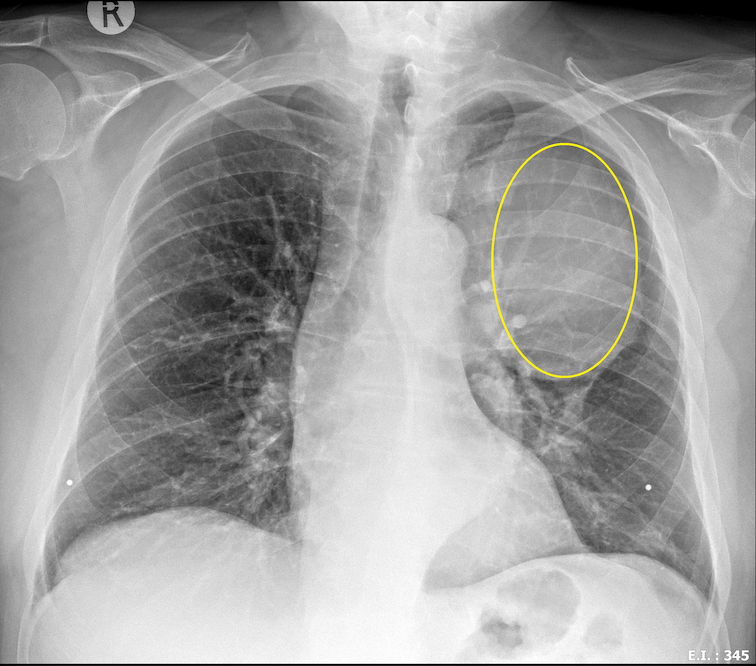

After intensive tests, scans and a huge operation to remove a tumour (15 x 10 x 10cm) he was diagnosed with a rare and aggressive cancer, called, Myofibroblastic Sarcoma. After more intensive tests and consultations with his oncologist and medical team, a specialized targeted therapy treatment has been recommended called immunotherapy.

What makes this campaign unique and urgent is that while awaiting treatment a new sarcoma (2 x 3 x 3 cm) has been identified on his latest CT scan, 2 months post operation. Importa...